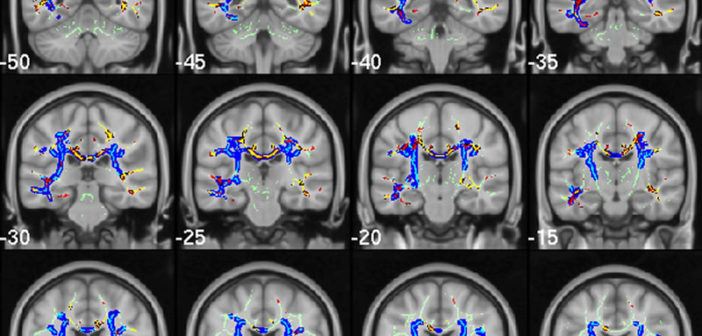

Brain scan. Image from Acosta-Cabronero et al.

This study is just one example of the vast Alzhimeimer’s research currently underway. For example, this past Wednesday we published a brain imaging study investigating potential biomarkers for Alzheimer’s that could facilitate early diagnosis, from Julio Acosta-Cabronero of the University of Cambridge and colleagues, and in September, we published a paper describing genetic signatures in mitochondrial DNA associated with a reduced risk for the disease from a group led by John Kauwe of Brigham Young University.

Acosta-Cabronero J, Alley S, Williams GB, Pengas G, Nestor PJ (2012) Diffusion Tensor Metrics as Biomarkers in Alzheimer’s Disease. PLoS ONE 7(11): e49072. doi:10.1371/journal.pone.0049072